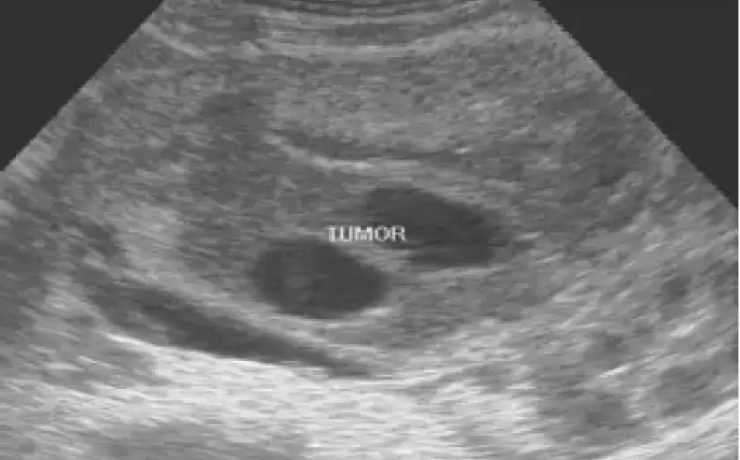

El objetivo del presente artículo es demostrar que la medición ecográfica del cordón umbilical es un factor que puede predecir la macrosomia fetal. Para lo cual se llevo a cabo un estudio descriptivo, observacional en mujeres gestantes a término cuyos factores de inclusión fueron gesta de 37 semanas, producto único